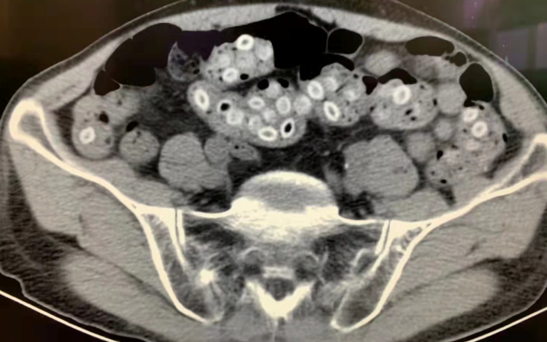

老太太平時身體很好,做起家務活來非常麻利。三天前的午後,老太太出現有下腹部陣發性絞痛,同時伴隨有嘔吐、腹瀉、畏寒、發熱。當時沒有特別重視,以為是吃壞了什麼東西,過幾天就自然好了。直到一天前,症狀愈發危重,去到當地醫院就診,一查CT,情況不妙——大腸破了,但是什麼原因導致的不得而知。醫生告知家屬病情加重,隨時有生命危險,而此時老太太精神狀態也變得疲軟,心跳血壓也明顯升高,商量後立刻轉至浙大二院。

經過ICU的接診醫生徐鵬一輪查體後,快速判斷老太太有休克徵兆,目前結腸穿孔原因不明。腸道里面含有大量的消化液以及大量的細菌,穿孔後透過破裂的口子進入腹腔並在裡面繁殖;腹腔裡面出現大量膿液之後,引發瀰漫性腹膜炎,炎症刺激會引起不能忍受的劇烈絞痛,還會伴隨有噁心嘔吐,寒戰高熱,嚴重可導致休克和死亡。